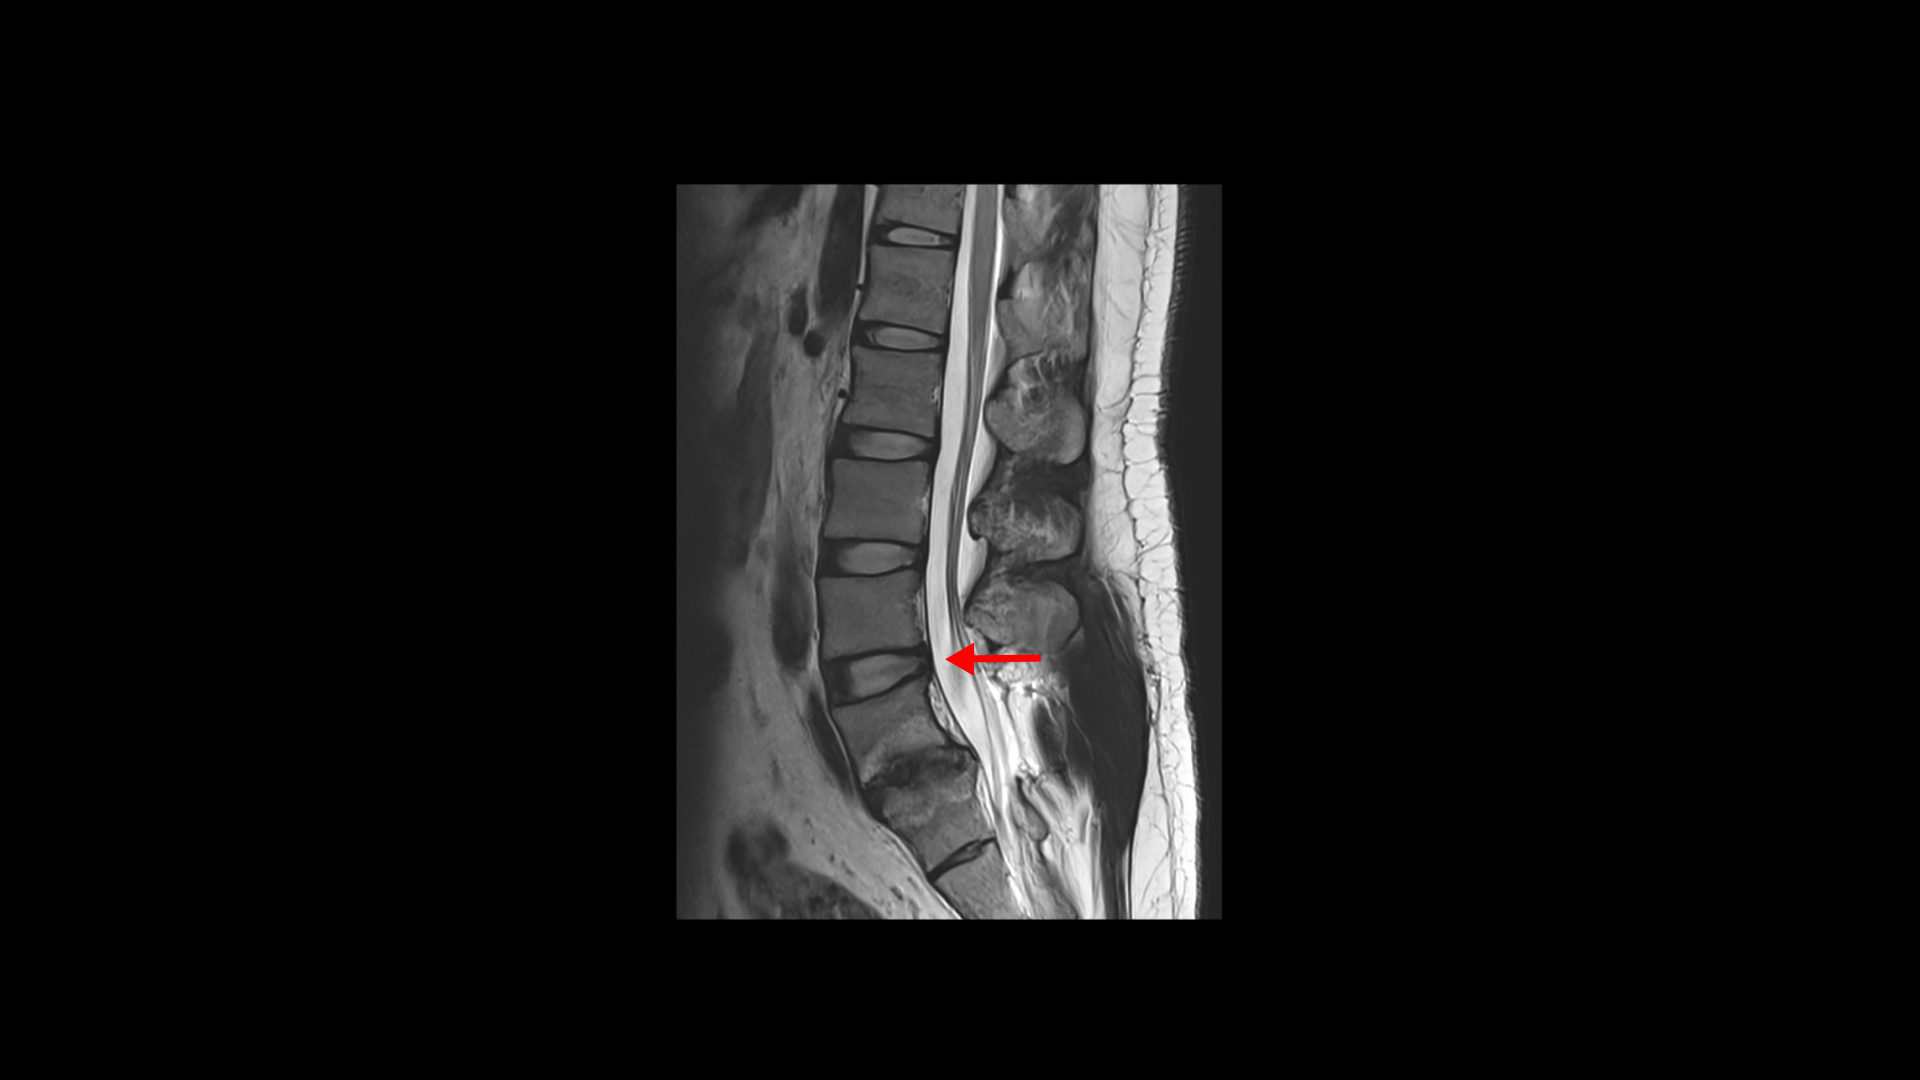

이분은 21살 때 척추분리증과 허리디스크 파열로 척추유합술을 받았습니다.

수술은 깨끗하게 잘 되었다는 얘기를 들었고 실제로 수술 후 2년간은 괜찮았습니다. 그러나 수술 후 2년이 지나면서 점점 허리, 엉덩이, 골반 부위가 뭉치면서 아파지고 계속 심해져서 결국 종아리와 발목까지 아프게 되었고 누웠다 일어나기도 힘들고 허리를 구부리는 것도 힘들고 오래 걷기도 어려워졌습니다. 대학병원에서는 약 처방 외에는 해줄 게 없다고 했고 다른 척추 병원들은 시술이나 주사치료를 하라고 해서 받았지만 효과는 제한적이었습니다.

그런데 척추유합술 후 또는 척추감압술 후 이렇게 아픈 환자분들이 매우 많습니다. 척추수술 후에 아픈 이유는 여러 가지가 있을 수 있지만 이 환자분은 명확하게 신경의 문제가 아닙니다. 첫째, 수술 직후 2년간 결과가 좋았었고, 그건 신경 감압이 잘 되었고 신경 감압 효과가 즉시 잘 나타났다는 의미입니다. 또 2년 후에 다시 아픈 이유도 우리가 흔히 얘기하는 인접 분절 질환도 아닙니다. 척추유합술을 하고 나면 몇 년 후에 수술 부위 위나 아래 마디에서 문제가 생기는 경우가 많습니다. 그걸 인접분절질환이라고 합니다. 그런데 이 환자분은 보시다시피 위 마디의 디스크도 깨끗합니다. 그럼 무슨 이유로 아픈 걸까요? 당연히 근육 문제입니다.

눌린 신경이 깨끗이 잘 풀려 있으면 근육 문제 외에 다른 문제를 생각하기 어렵습니다. 수술 후에 허리 유합으로 인한 허리 기능이 떨어지고 수술로 인한 허리 근육 손상도 있기 때문에 허리 근육과 골반, 엉덩이 쪽 근육들이 뭉치고 굳으면서 상태가 안 좋아지니까 결국 아래쪽의 종아리와 발끝까지도 아픈 겁니다.